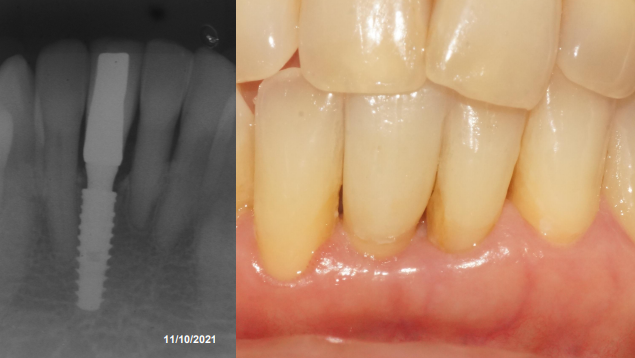

Paciente do sexo feminino, 65 anos, compareceu na clínica com o elemento 41fraturado. Porém, o fragmento estava estabilizado com resina acrílica, unindo-o aos dentes adjacentes. Foi solicitado o exame tomográfico e a anamnese foi realizada. Ao examinarmos a tomografia, optou-se pela exodontia e as instalações imediatas do implante Maestro de 3.5 X 11 mm e de uma prótese adesiva para aguardar o período necessário para o carregamento do implante. A terapêutica medicamentosa utilizada foi a administração de antibiótico por sete dias, acompanhado do uso de anti-inflamatório durante três dias após o procedimento cirúrgico.

O fragmento coronário e a raiz residual foram removidos e após a curetagem do alvéolo iniciou-se a fresagem do mesmo, seguindo o protocolo de instalação do implante Maestro para o mesmo ser ativado de forma precoce (35 dias após a instalação). Utilizamos a fresa lança helicoidal e na sequência foi utilizada a fresa cônica de 3.5, ambas as fresas com rotação de 600 RPM. Após a fresagem, o implante Maestro de 3.5 X 11.0 mm foi inserido no alvéolo, atingindo um torque de instalação de 25 Ncm, seguindo assim o protocolo de instalação do implante Maestro para carga precoce. Na sequência, foi realizada a sutura e a prótese adesiva foi instalada.